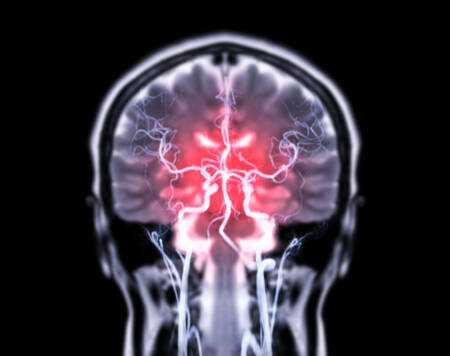

Condição silenciosa e potencialmente fatal, o aneurisma cerebral ocorre quando há uma dilatação anormal em uma artéria do cérebro. Esse “inchaço” cria uma bolsa que pode se romper a qualquer momento, com consequências graves, como derrames ou até a morte.

O desafio está no diagnóstico precoce, já que, na maioria das vezes, o aneurisma não apresenta sintomas claros. Porém, especialistas alertam para sinais e fatores de risco que merecem atenção redobrada.

Apesar de silencioso na maioria dos casos, o aneurisma cerebral pode causar sintomas quando atinge um tamanho maior ou pressiona estruturas do cérebro. Um dos sinais mais comuns é a dor de cabeça súbita e intensa, descrita por pacientes como “a pior dor da vida”.